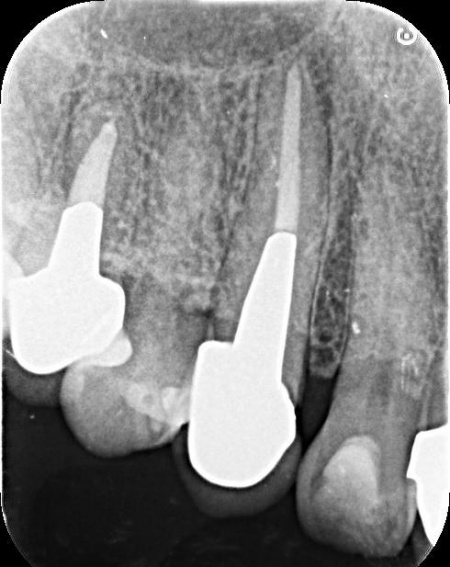

| 診断 | 拝見したところ、右上の犬歯には被せ物が装着されていました。 被せ物が装着されていると、レントゲン検査で歯の内部の状態を正確に確認することは困難です。 そこで、原因を詳しく調べるため被せ物を慎重に取り外し歯の内部を確認したところ、歯根が縦方向に割れる「歯根の垂直破折」が認められました。 また、このまま放置すると痛みや腫れが悪化し周囲の組織にも影響が及ぶ可能性があるため、抜歯が必要ですが、歯を抜いたままにすると隣の歯が動いて噛み合わせや歯並びに影響が出るおそれもあります。 以上のことから、抜歯したあとに歯を補う治療が必要と診断しました。 |

治療中